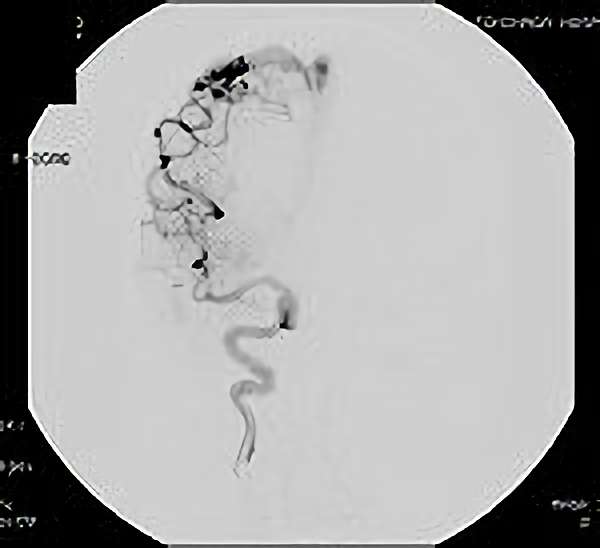

脳血管撮影

手術前

手術後

脳血管撮影により完全除去が確認された